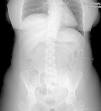

ResultadosEn siete pacientes, con una mediana de edad de 46 años (40-71), fue necesaria la realización de algún gesto quirúrgico sobre el uréter o la vejiga. Cuatro pacientes fueron intervenidas por recurrencia de la enfermedad ovárica, otras 2 pacientes la indicación fue el rescate quirúrgico y en una paciente se administró quimioterapia sistémica neoadyuvante previa a una primera cirugía citorreductora (cirugía de intervalo). En 4 de ellas existía afectación tumoral directa del tracto urinario inferior (fig. 1). Esta última paciente presentaba, previamente a ser remitida a nuestro centro, una ligadura iatrogénica del uréter izquierdo acontecida durante la realización de una laparotomía diagnóstica previa en otro hospital. En esta paciente, la ligadura pasó inadvertida durante la cirugía inicial y fue descubierta en el postoperatorio, precisando la colocación de una nefrostomía percutánea. Ninguna de las pacientes con afectación tumoral del uréter o la vejiga presentaba sintomatología urinaria preoperatoria. En las restantes dos pacientes se produjo una apertura accidental de la vejiga durante las maniobras de disección pélvica, que se resolvió intraoperatoriamente. El tipo de cirugía realizada en cada paciente está reflejada en la tabla 1. Los datos referentes a la edad, indicación quirúrgica, PCI, resultado tras la citorreducción, morbilidad postoperatoria, tiempo de seguimiento y estado actual de las pacientes incluidas en la serie están reflejadas en la tabla 2.

| 4 | Pelviperitonectomía, omentectomía y citorreducción del meso del intestino delgado. Resección de implante en antigua cicatriz | Resección 5 cm uréter distal. Ureteroneocistostomía (fig. 1) |

| 7 | Peritonectomía completa, histerectomía y doble anexectomía, colectomía subtotal, citorreducción del meso del intestino delgado, colecistectomía, esplenectomía. | Identificación de porción del uréter ligado, resección segmentaria con anastomosis ureteroureteral termino-terminal tutorizada con catéter doble J (fig. 2) |

Tres pacientes de la serie desarrollaron al menos una complicación postoperatoria. Una paciente desarrolló un derrame pleural cuantioso, secundario a la peritonectomía diafragmática practicada y fue necesaria la colocación de un drenaje torácico. Aparecieron 2 complicaciones urinarias, una complicación grado II (infección urinaria en una paciente) y otra de grado III (fístula urinaria), esta última en la paciente con ligadura iatrogénica del uréter en la que se practicó una anastomosis ureteroureteral (fig. 2). Esta última paciente desarrolló además una infección de la herida quirúrgica. Aunque la pieloureterografía percutánea a través de la nefrostomía demostró la ausencia de fuga en el postoperatorio previo al alta hospitalaria, fue necesario el reingreso de la misma por fiebre, detectándose en la TAC practicada de forma urgente, la presencia de una colección adyacente a la anastomosis ureteral compatible con urinoma. Dicha colección fue resuelta con la colocación de un drenaje radiológico, cesando progresivamente la emisión de orina por el mismo, siendo posible posteriormente su retirada. La fístula urinaria se resolvió de forma conservadora manteniendo la nefrostomía abierta durante 40 días, pudiendo proceder a su retirada tras la comprobación mediante urografía directa a través de la propia nefrostomía de la ausencia de fuga del contraste.